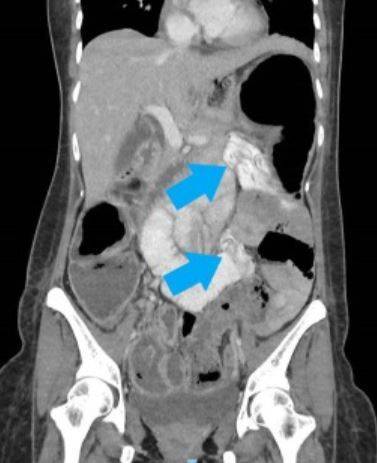

싱가포르 창이종합병원 의료진은 처음에는 A씨에게 위장염 진단을 내렸으나 이후 복부와 골반 CT 촬영 결과 대장 일부가 심하게 확장된 것을 발견했다.

또 입원 후 정밀 검사 결과 A씨의 백혈구 수치가 증가해 있었고, 복막염·패혈증 소견도 보였다고 한다. 의료진은 A씨가 기생충에 감염된 것 같다고 판단해 긴급 수술을 진행했다.

응급개복술 시행 결과 의료진은 A씨의 장 수많은 부위에 궤양, 천공(구멍)이 생긴 것을 확인했다. 이로 인한 고름성 복막염도 번진 상태였다.